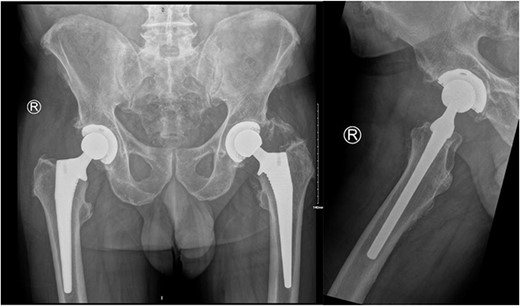

Our patient is a 74-year-old male who underwent primary total hip replacement for right hip pain. This was performed using a collared, fully hydroxyapatite-coated, uncemented stem, as well as an uncemented acetabular component with a ceramic-in-polyethylene bearing surface (Corail-Pinnacle, Depuy-Synthes, IN, USA). His recovery was uneventful until 6 weeks postoperatively when he presented to his routine outpatient appointment with significant erythema, swelling, and tenderness over his right hip wound. This was associated with difficulty weightbearing on the operative side due to discomfort. His background medical history included polymyalgia rheumatica for which he took Methotrexate 7.5 mg weekly, Folic acid 5 mg weekly, Celecoxib 200 mg BD, and pre-diabetes which was diet controlled. His other medical history included prostate cancer in remission since 2012, renal calculi, dyslipidaemia, and hypertension. He had a contralateral total hip replacement performed in 2020 (Fig. 1). He had no known drug allergies. At baseline, he was independently mobile. He was a non-smoker and non-drinker.

Preoperative AP pelvis and lateral right hip radiographs of our patient showing right hip osteoarthritis and previous left THR in situ.